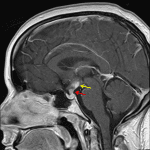

Indication: Diabetes insipidus, status post brain biopsy

- Abnormal enhancement and thickening of the pituitary stalk and of the hypothalamus bilaterally

- Linear area of T2 hyperintensity extending through the left frontal lobe to the hypothalamus, consistent with a biopsy track

- Lymphocytic hypophysitis (infundibulohypophysitis)

Abnormal enhancement and thickening of the pituitary stalk and of the hypothalamus bilaterally, for which the differential diagnosis includes lymphocytic hypophysitis, neoplasm such as lymphoma or germinoma, or granulomatous process such as sarcoidosis or Langerhans cell histiocytosis.